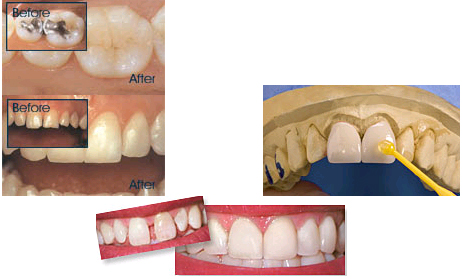

Dental Bleaching ![]()

Tooth Whitening treatments have turned into one of the hottest themes in dental esthetics. Every day new techniques enter the market making this treatment available for almost each patient. There are many products and treatments offered over the counter; however none of them are as efficient or long term as those provided by a Dental professional. Broken teeth, poorly fitting old restorations can present negative effects over the teeth when a non controlled bleaching is done. These types of problems can be avoided with a comprehensive oral examination done by your dentist. After the examination, Dr’s Stedem can give you the best treatment plan to ensure your new beautiful white smile.

Restorative and Esthetic Dentistry ![]()

New generations of restorative dental materials help us to offer our patients beautiful and esthetic restorations. Even if you have broken teeth, old restorations with different shades or colors, or one or more teeth are missing. The use of composites or porcelain over decayed teeth and restorations can make a tremendous change in your smile. Each individual case must be evaluated first by our team of specialists in order to deliver the best treatment options.

A crown is a type of restoration that will be cemented over a prepared tooth looking to restore the form and function of the original. Decayed, broken and/or pigmented teeth compromise the normal function and esthetics for the patient. A bridge is a restoration that will replace a missing tooth making use of the two teeth adjacent to the missing tooth which will support the missing tooth. Both crowns and bridges can be made from multiple types of materials, from less to more esthetic. Each patient must be first evaluated to determine the best treatment option.